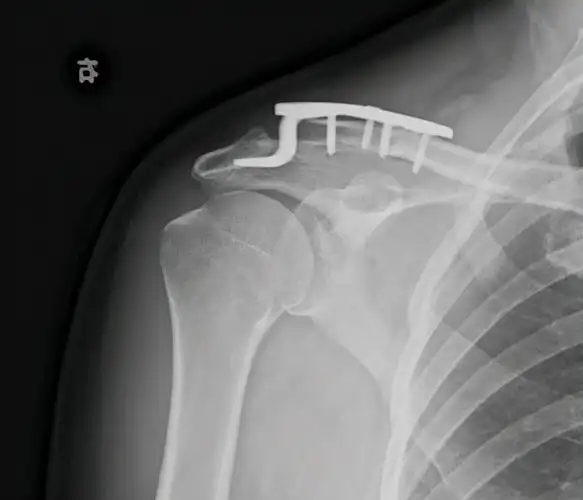

肩锁关节脱位术前术后

右肩锁关节脱位纽扣钢板固定